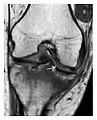

Fatigue fractures

Fatigue fractures occur when healthy bone is exposed to repeated stress. The bone is a living tissue, with the capacity to repair itself; fatigue fractures occur when repetitive injuries exceed the repair capacity of the bone. This type of fracture does not occur as a single event but rather incrementally as a sequence of cellular events that begin with increased osteoclastic activity. Microfractures occur later and are accompanied by bone marrow edema, which can be detected on MRI. This stage appears on MRI as an isolated bone marrow edema pattern without a fracture line and is called stress reaction. Then, periosteal new bone forms and may be visible on radiography. Full cortical fractures occur if the repetitive stress continues. Only timely detection and appropriate management can interrupt this sequence.[1]

Fatigue fractures are more frequent in women which may be due to the relatively smaller bones of women. Moreover, pregnancy is a well-recognized risk factor for femoral neck fatigue fracture. While fibular and metatarsal fractures have a low risk of complications, other sites including the femoral neck, midanterior tibia, navicular, talar, and other intraarticular fractures are prone to complications such as delayed union, nonunion, and displacement. The site of the insufficiency fracture may be specific to the activity: for example, rugby and basketball players are more prone to navicular fractures, while gymnasts have a higher risk for talar fractures (Figure 7). Long distance runners are at increased risk for pelvic, tibial (Figures 8 and 9), and fibular fractures. In the military, calcaneus (Figure 10) and metatarsals are the most commonly cited injuries, especially in new recruits. Billiard players are at risk for upper limb fractures (Figure 11).[1]

a

b

Figure 7: Fatigue fracture of the talus in a 25-year-old male basketball player with right hind foot and ankle pain, without history of trauma, and a normal initial radiograph (not shown). (a) One-month followup lateral radiograph shows normal appearance. (b) Sagittal T1-weighted MRI shows an irregular fracture line (arrow) within an ill-defined area of hypointensity corresponding to bone marrow edema.[1]

Radiographic examination usually shows delayed signs of fracture up to 2 to 3 months after initial injury. In a bony region with a high proportion of cancellous bone (e.g., femoral neck), a fatigue fracture appears as an ill-defined transverse sclerotic band (in contact or close to the medial cortex), with a periosteal thickening appearing at a later stage. In case of continued stress, a fracture line through the thickened cortex and a region of sclerosis may be observed. MRI is of great value for early diagnosis and displaying bone marrow edema, while scintigraphy is useful for showing increased metabolic activity within the bone. However, MRI is preferred since scintigraphy lacks specificity. In case of isolated bone marrow edema in MRI without a fracture line, the diagnosis of fatigue fracture may be more complicated, and other conditions such as transient edema and osteoid osteoma need to be excluded. Additional imaging by CT is warranted in such cases.[1]